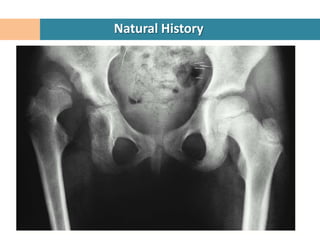

Natural History

Over the age of 6 months spontaneous resolution of dysplasia is unlikely

Usually more aggressive treatment is required compared with younger children.

Older children tend to have more advanced changes in the soft tissues and bony

structures.

Changes in acetabulum

Ossification is delayed

Shallow,

Anteverted

Deficient anterolaterally.

Changes in Femoral Head

Delayed ossification

Exaggerated femoral anteversion.